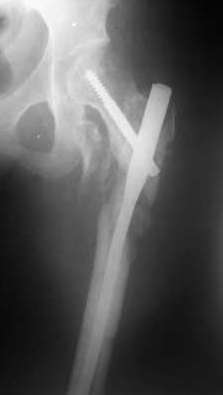

Мы закончили репозицию отломков бедренной кости в аппарате (рис. 1, 2) у нашей пациентки и на прошлой неделе сделали ей вторую операцию. Штифт удалось ввести закрыто. Верхний шеечный винт держался очень плохо, поэтому мы его убрали и решили не ставить. Нижний держал очень плотно. Рентгенограммы после операции прилагаю (рис. 3,4). Пока не получилось сделать нормальный аксиальный снимок (больная с трудом сгибает и отводит ногу в тазобедренном суставе). Пока сделали боковую проекцию в положении на здоровом боку со сгибанием здоровой ноги.